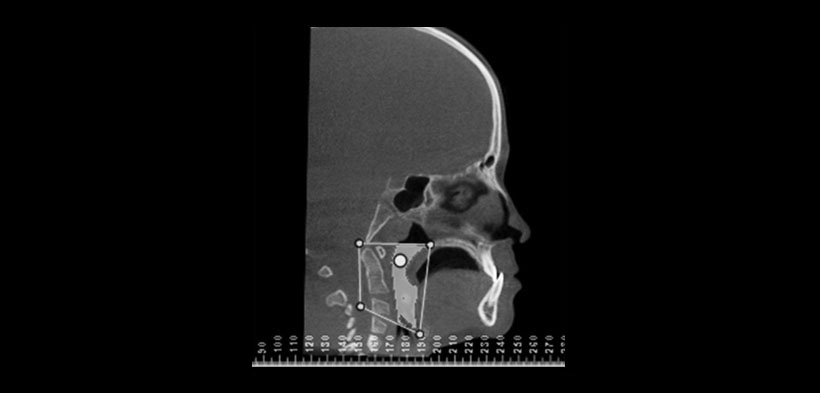

Fig. 3. Se muestran las fronteras del volumen de las vías respiratorias. El borde superior incluye el punto de la espina nasal posterior a basion más posterior, mientras que el borde inferior se define por una línea desde el borde inferior de la base de la epiglotis a vertebra C3.